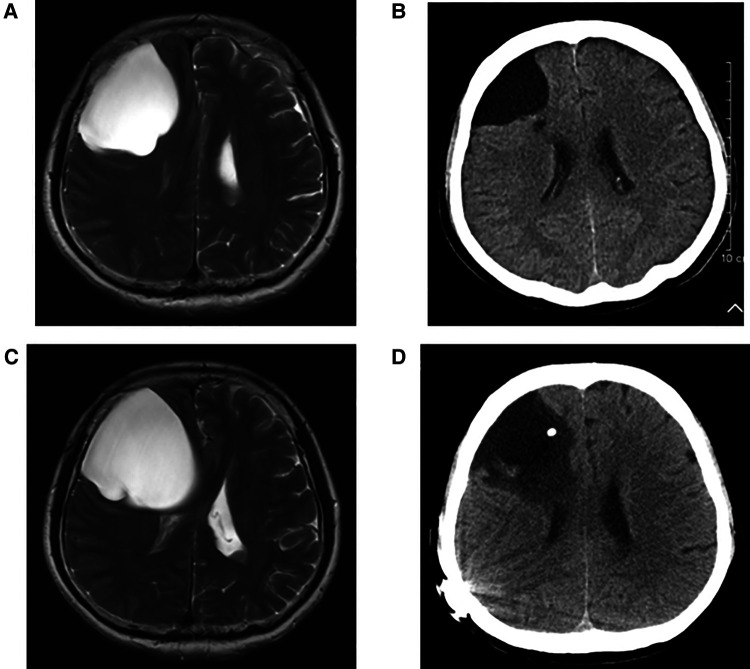

In group A, four patients presented with dizziness in the preoperative period; three of the four patients had relief of dizziness in the postoperative period. The three patients suffered from headache before surgery, and headache symptoms improved in all of them after surgery. However, two of the three patients had an increase in headache symptoms during the follow-up period (No. 3 and No. 4 patients). Their MRI showed the intracranial arachnoid cysts had grown larger than them in the preoperative period, and they then underwent intracranial arachnoid cyst-peritoneal shunt in our department (No. 4 patient's MRI and CT images are shown in Figure 2). Two patients presented with cerebellar ataxia in the preoperative period, and their symptoms improved after surgery. One patient had epileptic symptoms before surgery, and his frequency of seizures decreased after surgery (Table 3).

Figure 2.

(A) Preoperative T2 MRI image of No. 4 patient. (B) CT image of No. 4 patient at 1 year and 4 months after neuroendoscopic surgery. (C) T2 MRI image of No. 4 patient at 2 years and 6 months after neuroendoscopic surgery. (D) CT image of No. 4 patient after intracranial arachnoid cyst-peritoneal shunt.

The maximum diameter of intracranial arachnoid cysts in group A was 6.38 cm on average, and that in group B was 2.97 cm on average, which was significantly different between the two groups (Tables 1, 4). In group A, all of the patients' intracranial arachnoid cysts showed a remarkable reduction in cyst size during the follow-up period (e.g., No. 6 and No. 5 patients' MRI images are shown in Figures 1E–H). However, two patients' cysts recurred, and an intracranial arachnoid cyst-peritoneal shunt was performed. In group B, patients' intracranial arachnoid cysts were resected, then the brain tissue tends to return to the normal anatomical structure (e.g., No. 13 patient's MRI and CT images are shown in Figure 3), and the cyst did not recur during the follow-up period.